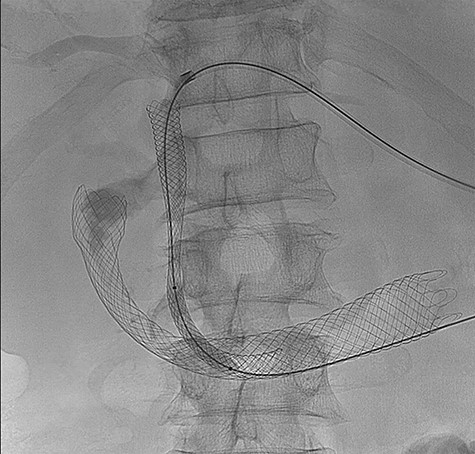

A retroperitoneal percutaneous biopsy of the retrocaval lymph node mass was performed without any complications. Awaiting histological diagnosis, his gastric outlet obstruction worsened, and hyperbilirubinemia increased to 317 umol/L, developed acute renal failure with creatinine rising to 484 umol/L and progressive anuria. The renal failure was believed to be multifactorial from malignancy and cholemic nephropathy that can be seen in patients with obstructive jaundice [2]. The patient was transferred to HDU (High Dependency Unit) for haemodialysis. Histopathology results confirmed a poorly differentiated high-grade RCC of clear cell subtype. Endoscopic examination performed confirmed an infiltrating obstructive duodenal mass and a self-expanding ‘Wallflex’ duodenal stent was inserted. As retrograde access for biliary stenting was near impossible, a percutaneous transhepatic cholangiography (PTC) was performed with anterograde stenting of the bile duct resolving the hyperbilirubinemia (Fig. 3). Over the following days the patient’s hyperbilirubinemia and renal failure normalized. He recovered uneventfully and was subsequently commenced on immunotherapy prior to discharge.

(PTC) Anterograde biliary stent through duodenal wall flex stent.